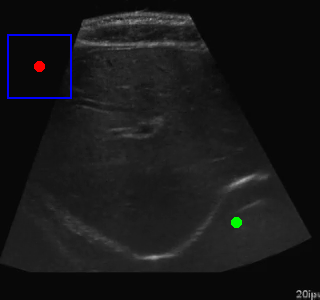

This project combines deep learning-based image segmentation with reinforcement learning to automatically navigate to regions of interest in ultrasound images. The system consists of three main components:

The trained agent successfully navigates to the centers of the segmented regions with a high success rate. The improvements to address oscillations significantly enhanced the agent's performance.